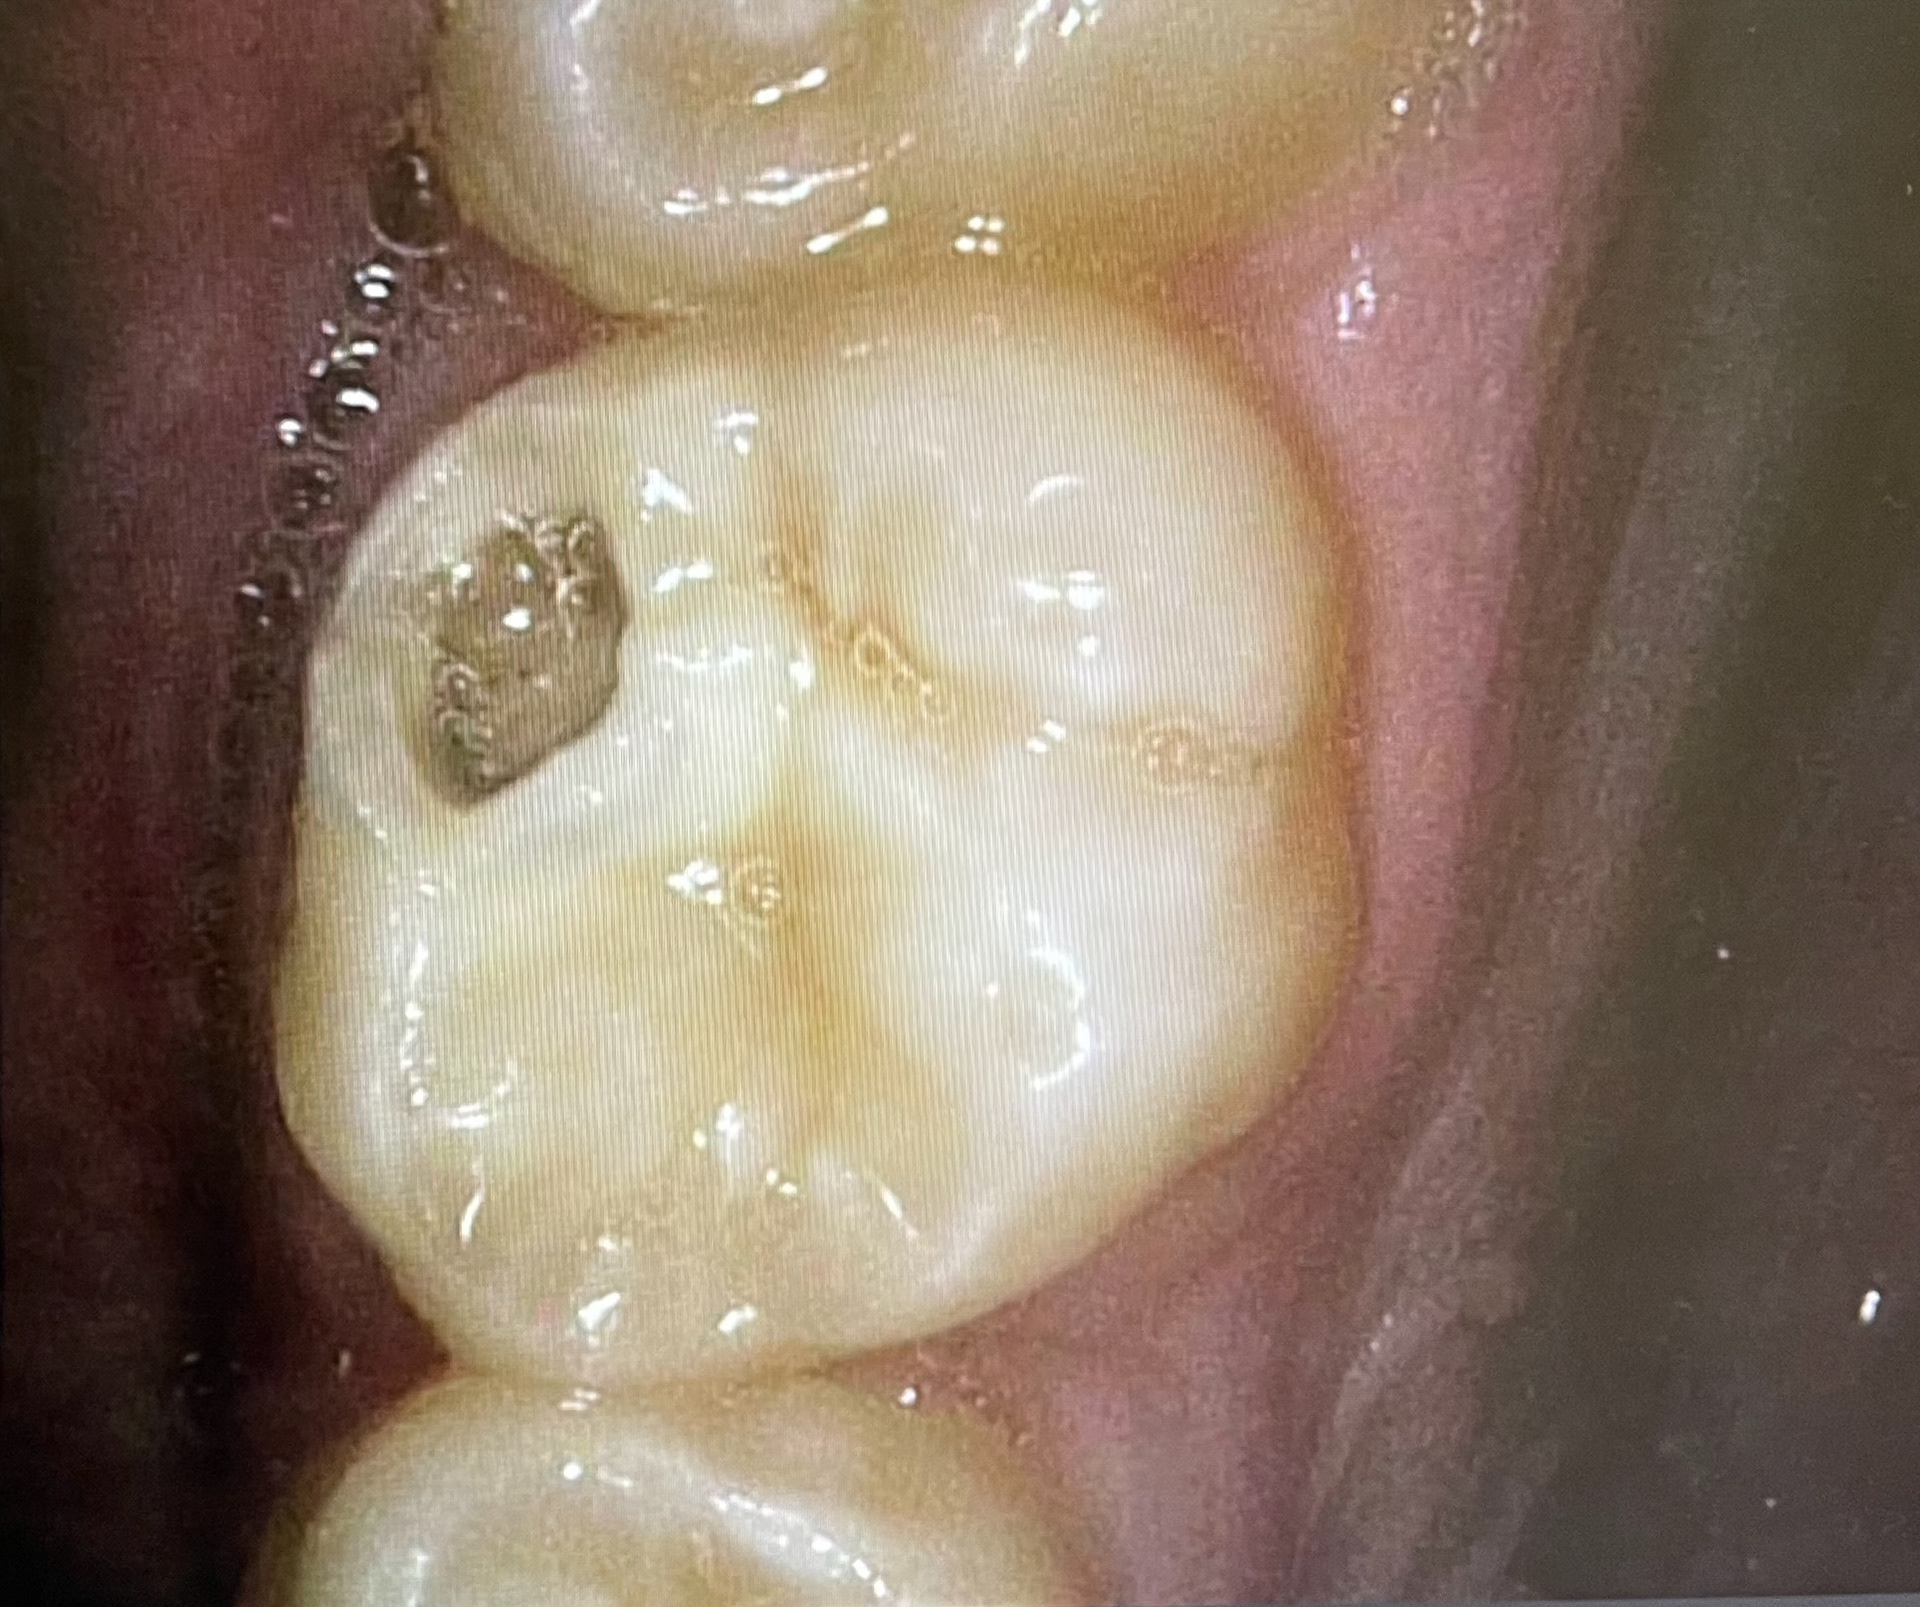

Initial